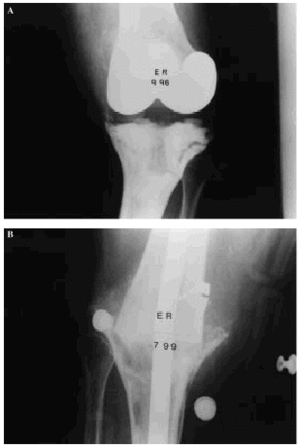

Entre diciembre de 1991 y marzo de 2000 se realizaron 21 artrodesis de rodilla mediante enclavado endomedular. El estudio está basado en el análisis retrospectivo de estos procedimientos y su evolución. De los 20 pacientes, en un caso se realizó artrodesis en ambas rodillas aunque no coincidieron en el tiempo; 15 fueron mujeres. La edad media, en el momento de la cirugía, fue de 67,8 años (mínimo 17 y máximo 82 años). La causa de la artrodesis fue el fracaso de la artroplastia en 18 casos, un osteosarcoma en metáfisis femoral distal en un varón de 17 años, una gonartrosis severa en una paciente con obesidad mórbida y artroplastia de la rodilla contralateral (Fig. 1) y, por último, una gonartrosis en un miembro afecto de poliomielitis.

Figura 1. Paciente con obesidad mórbida y artroplastia de rodilla contralateral. A: Radiografía preoperatoria. B: Radiografía a los 3 años de la cirugía, consolidación.